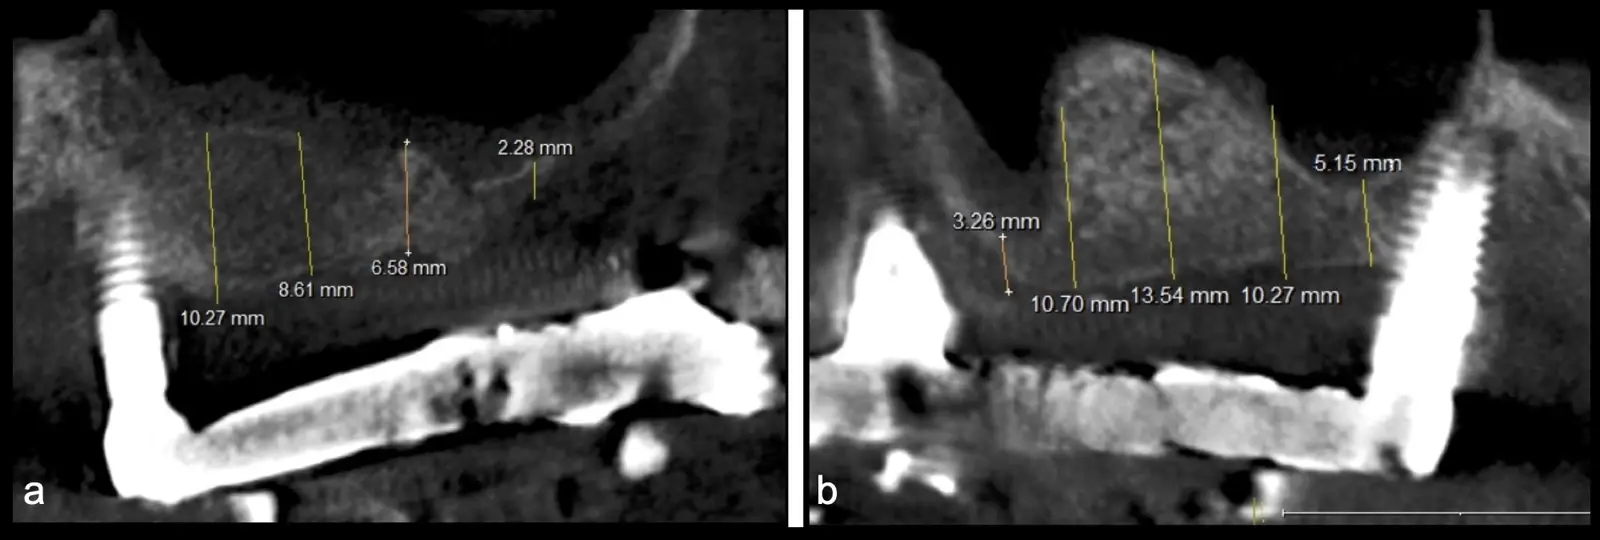

Figura 1. Incisión y levantamiento de colgajo a espesor total.

Figura 15. Incisión supracrestal y decolado a espesor total del lado izquierdo.